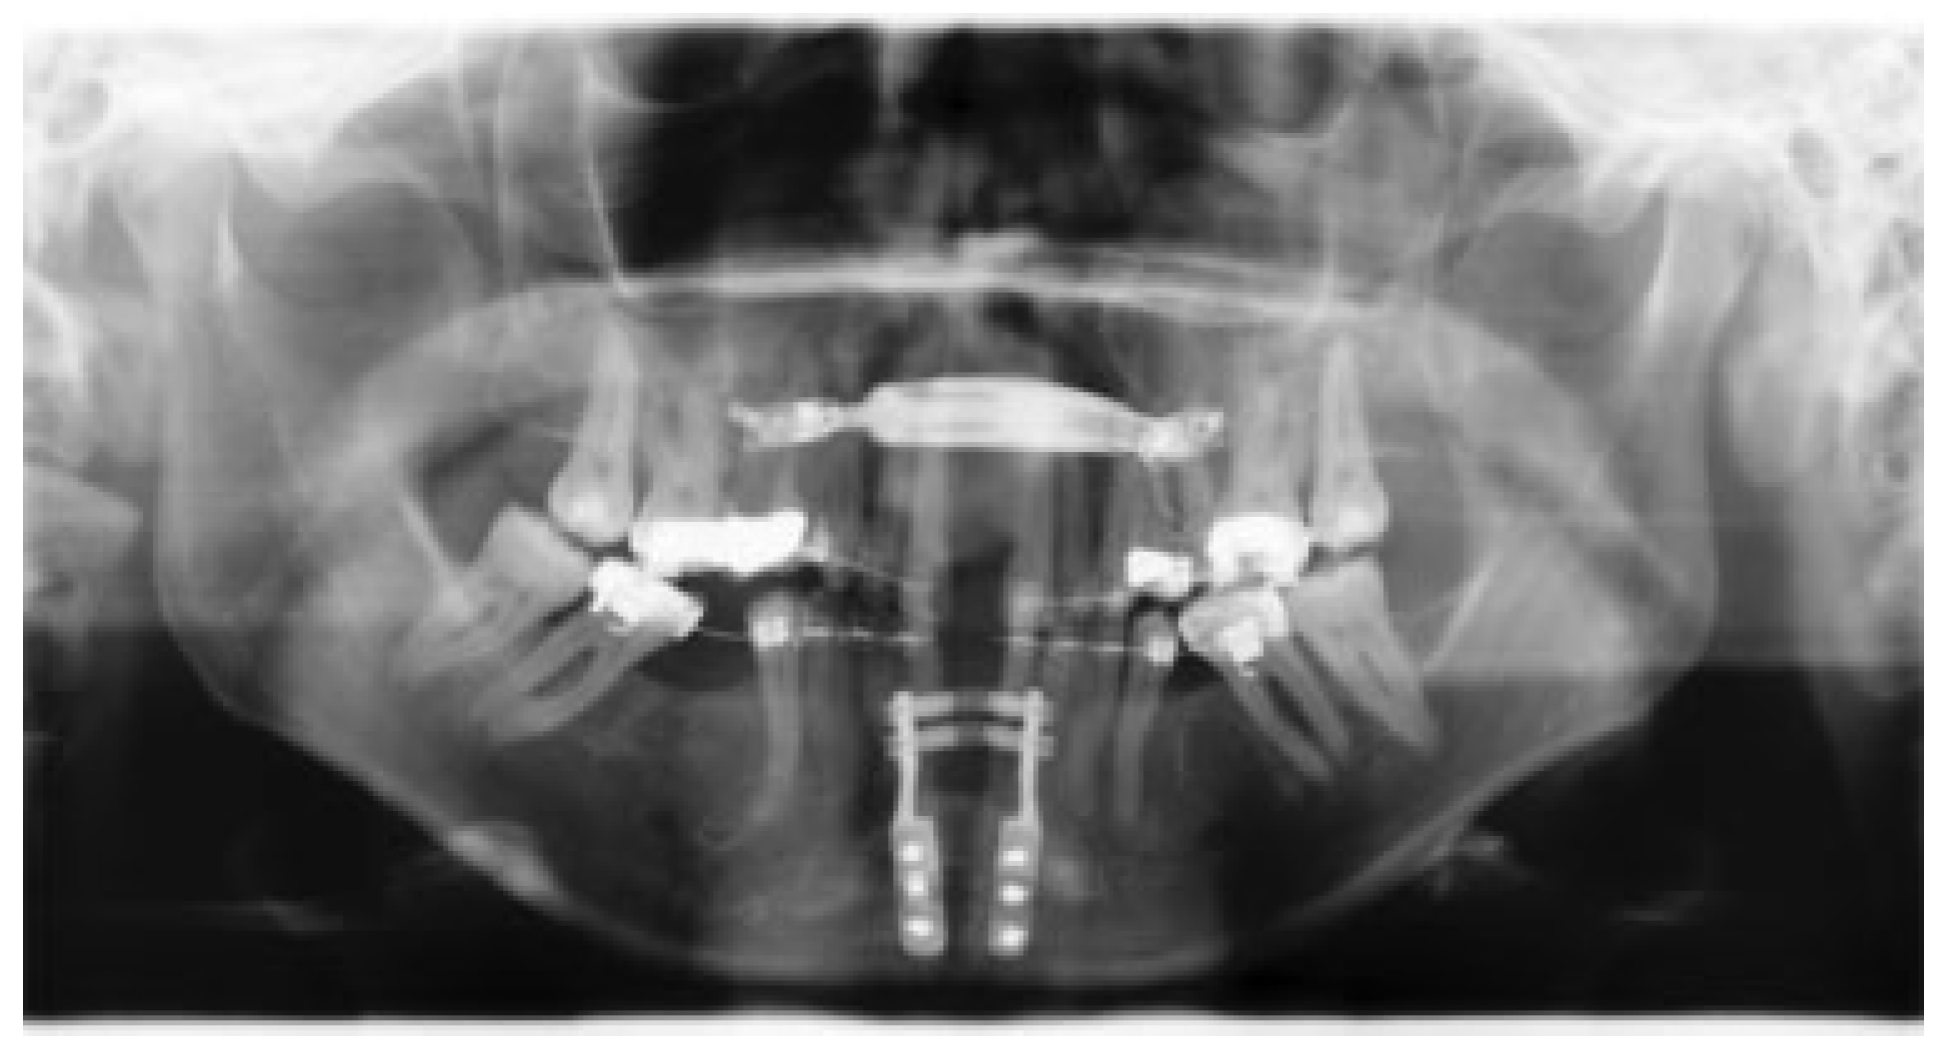

Complications that occurred included wound dehiscence, pressure ulcers, extraction of teeth, and reoperations (Table 3 and Table 4). Consequently, the CDS grade ranged from I to IIIb. Included in group I (37%) were wound dehiscence (13.7%), pressure ulcers (12.3%), (transient) sensory deficits (11%), and (transient) temporomandibular joint complaints (6.8%). The (transient) sensory deficiencies included hypo- and paraesthesia of the mental nerve as described in the patient records. The (transient) temporomandibular joint complaints included transient joint tenderness and clicking of the joint. Grade I also included some distractor-related complications. In one patient, the distracter bent at the end of the distraction period (Figure 1). Enough widening was achieved; however, the distraction gap was in V-shape. Another patient was activating the distractor in the wrong direction. Fortunately, it was observed on time and could be reversed. A grade II (2.7%) was scored in two patients who needed antibiotic treatment: in one case as a result of wound infection, and in the other as a result of severe gingivitis. In the latter case, the patient was too afraid to brush her teeth after the procedure. The IIIa grade (2.7%) was scored when a patient needed extractions of two teeth following periodontal decay after MMD and a second patient needed release of mucosal adhesions which emerged after MMD. The three patients who scored a grade IIIb complication (4.1%) needed a second surgical procedure under general anesthesia. In the first patient, the distractor type was too small to obtain adequate expansion of the mandible and a second procedure with a larger distractor was necessary. A second patient required remodeling of the chin because of a palpable distraction gap, which was corrected during the already planned bilateral sagittal split osteotomy procedure. A third patient suffered from an insufficient expanding distractor and a new distractor needed to be placed to achieve enough widening.

Figure 1.

Bended distractor and V-shaped distraction gap.